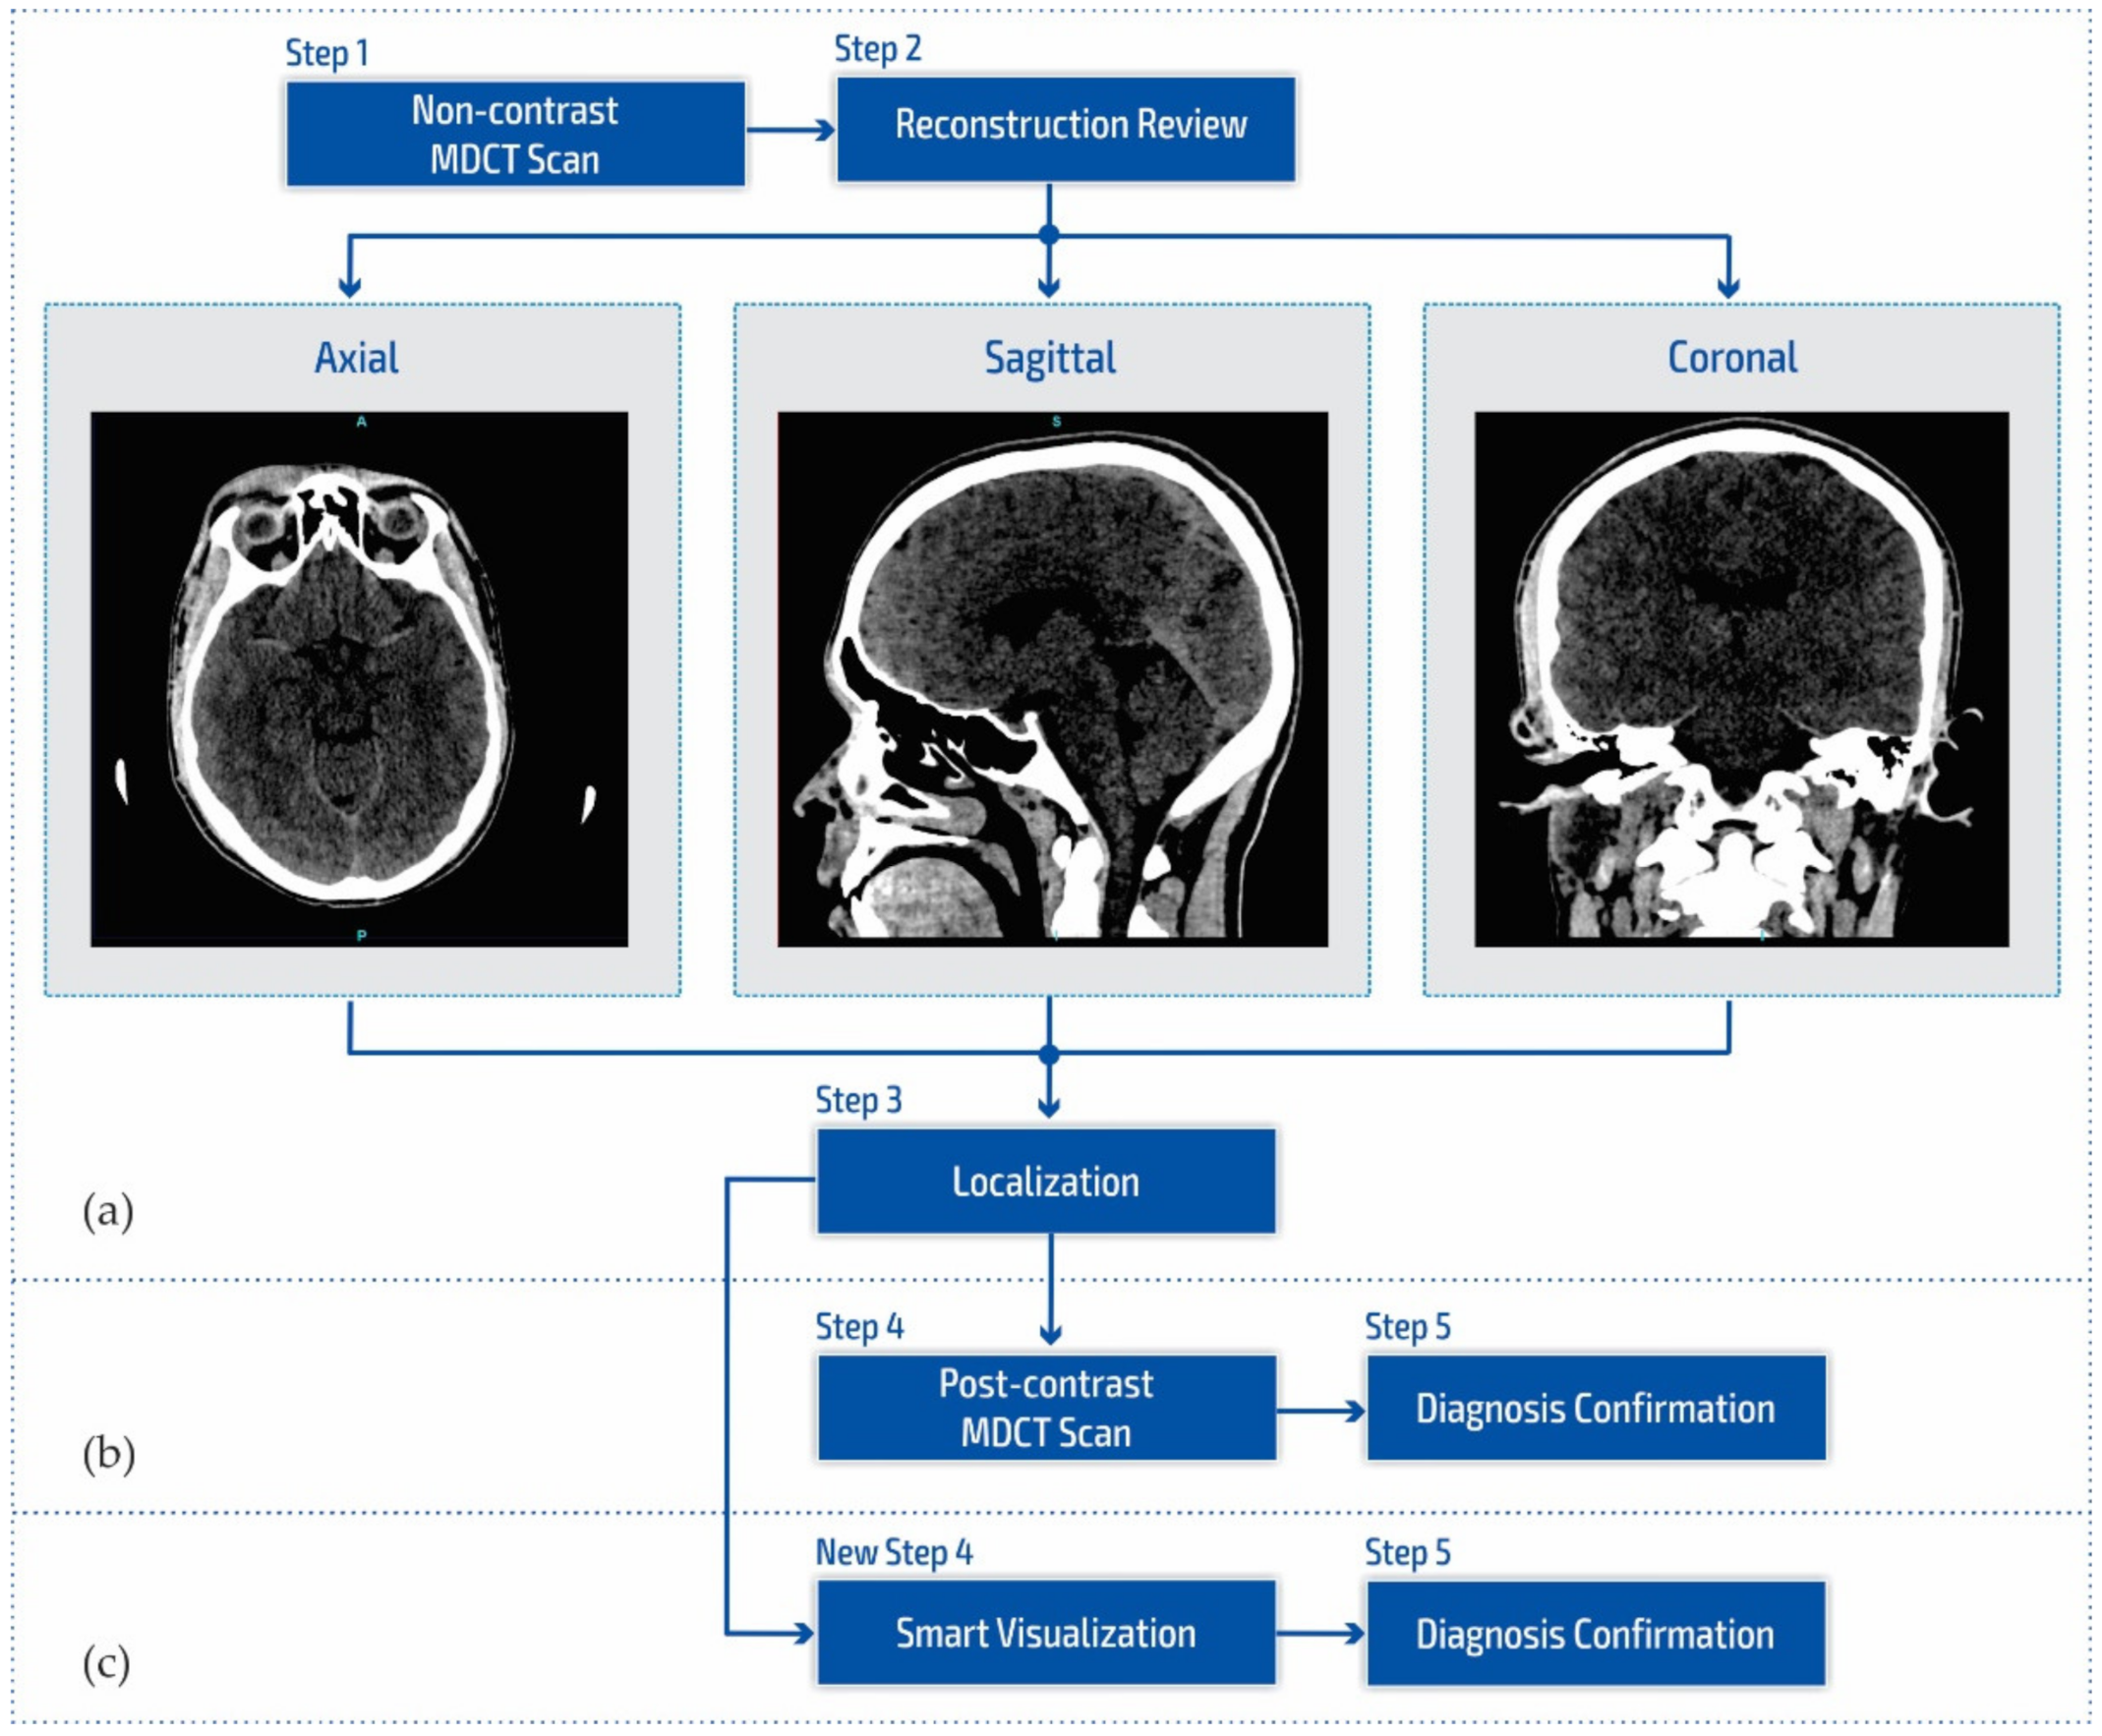

Figure 1a shows a block diagram of the standard neuroradiology diagnostics approach using a multi-detector computed tomography. Following MDCT diagnostics and a non-contrast MDCT endocranium scanning (Figure 1a, Step 1), a neuroradiologist examines the reconstruction in all three cross-section planes (Figure 1a, Step 2): (a) axial, (b) coronal, and (c) sagittal to determine the existence of pathological changes in density, classified as hyperdensity [39]; hypodensity [40]; and isodensity [41], to accurately determine the localization of the region of interest (Figure 1a, Step 3).

Figure 1.

Block diagram of (a) the multi-detector computed tomography method, (b) the post-contrast MDCT diagnostics method, and (c) the smart visualization (SVMI) method.

After determining the existence of a pathological change, the work of a neuroradiologist requires access to post-contrast MDCT diagnostics (Figure 1b, Step 4) to characterize the changes in the brain and develop a conclusion in the form of differential diagnosis and medical determination (Figure 1b, Step 5). Unfortunately, rescanning exposes the patient to the possible consequences of an additional influence of ionizing radiation due to its cumulative effect. Side effects can also be reflected in the patient’s allergic reactions to iodine that have not been previously determined. This includes the inability to use iodine contrast media in pre-existing and confirmed allergic reactions, which consequently refers the patient to MRI diagnostics that are not available to everyone because they have both absolute and relative contraindications. With the goal of successful treatment and diagnosis of brain diseases in patients, current research in MDCT and MRI diagnostics aims to characterize brain diseases non-invasively [42,43,44,45,46]. However, multi-detector computed tomography has some advantages concerning MRI diagnostics, enabling quantitative measures of deterioration of the blood–brain barrier that may be associated with tumor and neovascularization [42,43,47,48].

Due to the stated conditions and limitations in Figure 1b at Step 4, in order to prevent post-contrast scanning of the patient, a New Step 4 in Figure 1c is proposed which enables the smart visualization of medical images (SVMI) and a more precise presentation to neurologists of the localized changes in the patient’s brain at a determined cross-section of plane and slice.